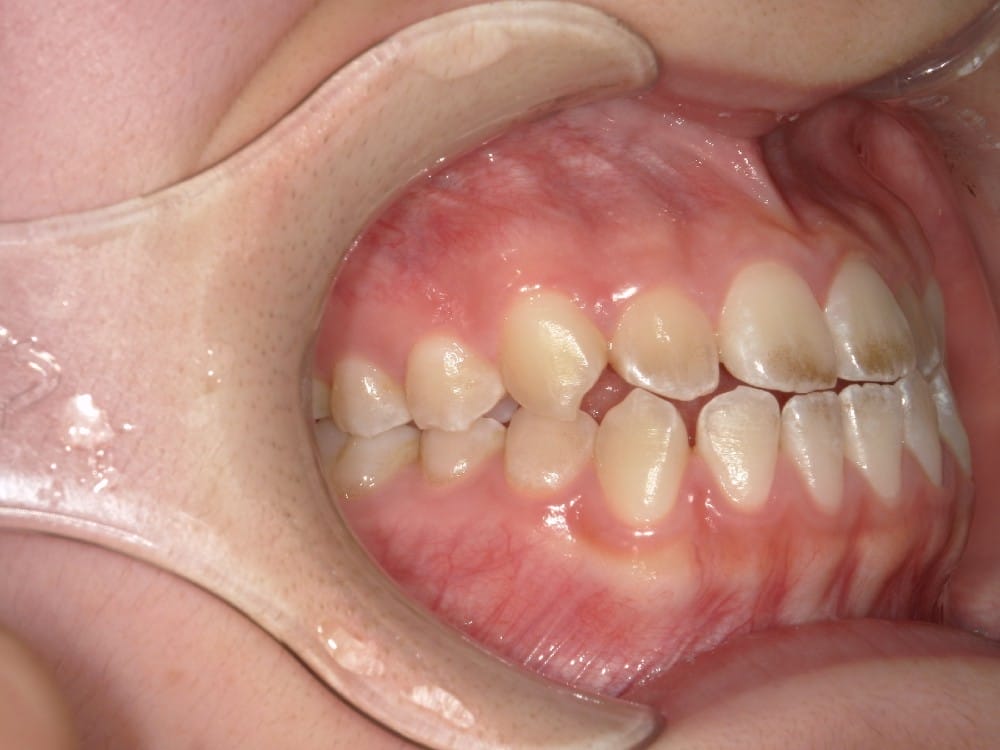

最後の画像のように奥歯のズレが1本以上あるケースでは、歯列矯正のみでの受け口の改善は困難と判断することが多いです。

(case3)

受け口は治ったけれど横顔は変化しなかったケースもあるので、紹介します。

30代の男性で、受け口とガタガタを主訴にご来院されました。

治療前の様子

分析しますと

- 骨格的な上下あごの前後差は重度

- 噛み合わせの位置も下あごの奥歯が半分くらい前にズレていた

- 上の前歯が前に傾斜、下の前歯が内側に傾斜しているにもかかわらず、受け口

というケースで、外科的な処置も検討するようなケースでした。

骨格的なズレや奥歯の噛み合わせのズレもあり、重度の受け口でしたが、なんとか歯列矯正のみで受け口を改善できると診断し、治療を開始しました。

先ほどの2ケースと同じように、患者さまに外科的な手術の選択肢も提示しましたが、希望されず、横顔の変化はおそらく起こらないことを納得の上、治療をスタートいたしました。

今回のケースも奥歯の移動量が大きいため、マウスピースだけでは難しいと判断し、カリエールとよばれる装置を補助的に使用し、上下の噛み合わせの前後関係を整えることで、手術を行わずに機能面と見た目の両方が改善することにしました。

治療後の写真です。

<治療前後の比較です>

正面から見た時の受け口は改善していますが、横顔の変化は軽微かほとんど起こっていません。

同じように治したケースでも横顔の変化には差があります。

だからこそ、治療前に「どこまでを目標にするのか」をしっかり共有し、噛み合わせ改善を軸に治療を進めることが大切になります。